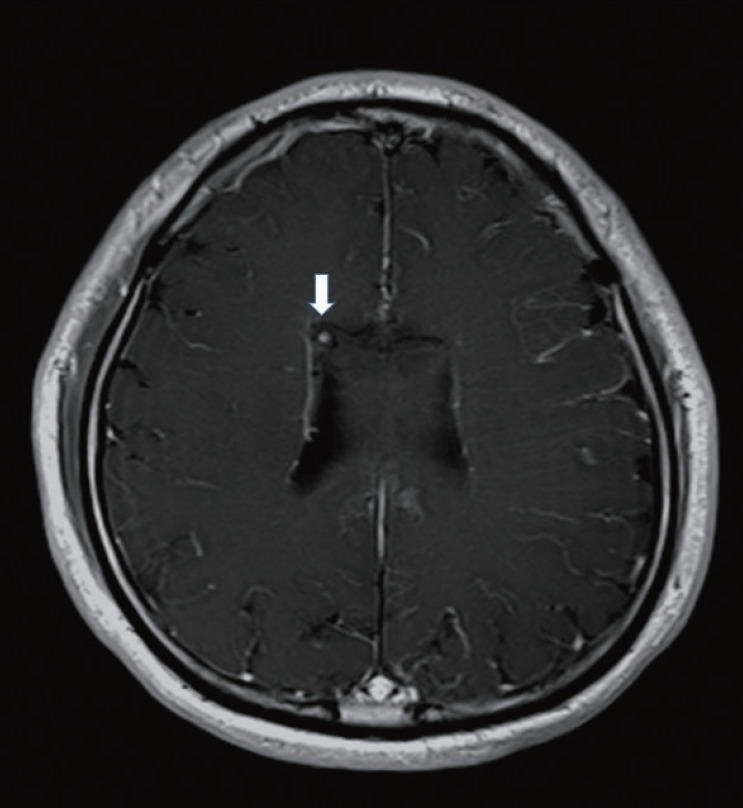

Fig. 2.

Axial view of enhanced T1-weight magnetic resonance image (MRI) is showing abnormal vascular spot point which can be origin of intraventricular hemorrhage in lateral wall of the right frontal horn (white arrow).

Computed tomography (CT) of the head at admission revealed an intraventricular hemorrhage (IVH) extended from a focal hemorrhage in the body of the corpus callosum (Fig. 1). He was young and had no risk factor for intracerebral hemorrhage (e.g., hypertension, diabetes). Therefore, enhanced magnetic resonance images (MRI) was performed. We found enhanced vascular spot point which can be origin of IVH in lateral wall of the right frontal horn (white arrow in Fig. 2). Trans-femoral cerebral angiography (TFCA) was performed. A left internal carotid injection demonstrated a total occlusion of the distal internal carotid artery with numerous basal collateral vessels. A right internal carotid injection revealed a total occlusion of the proximal A1 segment, and the distal anterior cerebral artery territory was supplied with ethmoidal collateral vessels. All these findings were consistent with MMD (Fig. 3). A ruptured saccular aneurysm which causes IVH was found in the LSA arising from proximal one third of right middle cerebral artery (MCA) (white arrow head in Fig. 4). Initially, conservative treatment was selected based on his neurological condition, with expectation of spontaneous regression. A repeat TFCA performed on post-hemorrhage day 18 demonstrated persistent filling of the aneurysm, and the patient’s clinical status was unchanged.